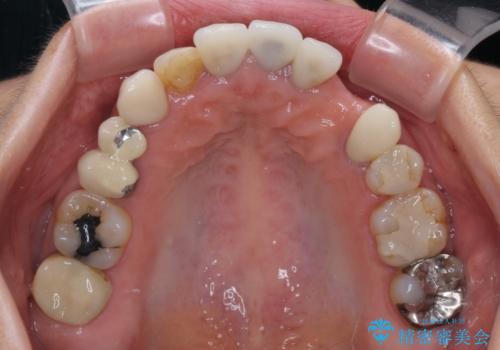

- 他院で矯正治療を終えたものの、むし歯や欠損部の治療が進められないとのことで来院された患者様です。

欠損部や、銀歯やむし歯の大きな歯はセラミッククラウンやブリッジに、小さいむし歯はセラミックインレーにて治療を行うこととしました。

歯肉の状態がとても、短期間でスムーズに治療を終えることができました。